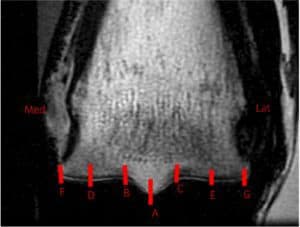

Researchers Review Subchondral Bone Remodeling in Racehorses

Bone turnover in horses rested after intense training was better than in those in consistent intense work.